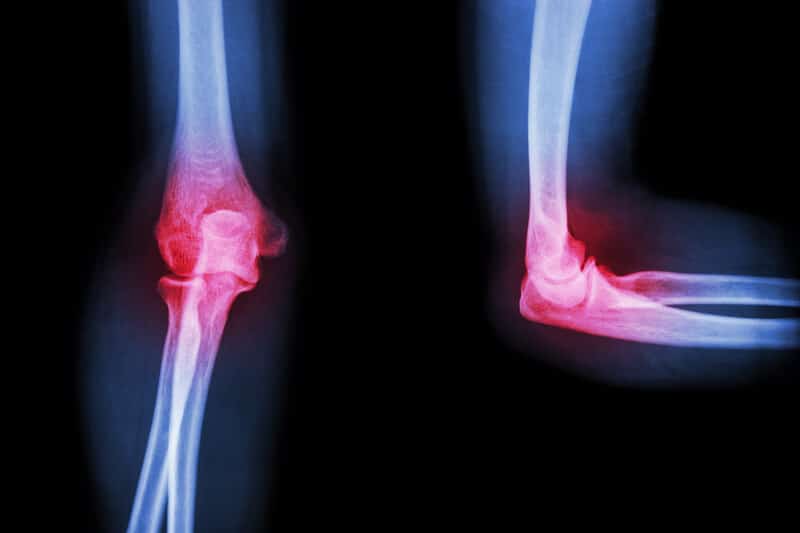

We have seen many patients over the years with problem elbows. We see some whose problems have extended beyond a tennis or golfer’s elbow problem, into one of osteoarthritis, and a recommendation for an elbow replacement surgery. Elbow replacement surgery is certainly not as popular as knee, hip and shoulder replacement, but it is performed and by the acknowledgement of surgeons, it is a tricky surgery.

As the elbow is a hinged joint similar to the knee, elbow osteoarthritis share many of the same characteristics and treatment suggestions that someone with knee osteoarthritis would get. There are treatments for pain that include pain medications and anti-inflammatories. Physical therapy and exercise would be recommended if the elbow locks up. Like the knee, extensive elbow braces and sleeves may be worn. Eventually if an MRI is “bad” enough, an arthroscopic procedure would be recommended. Ultimately the medical journey would end with an elbow replacement.